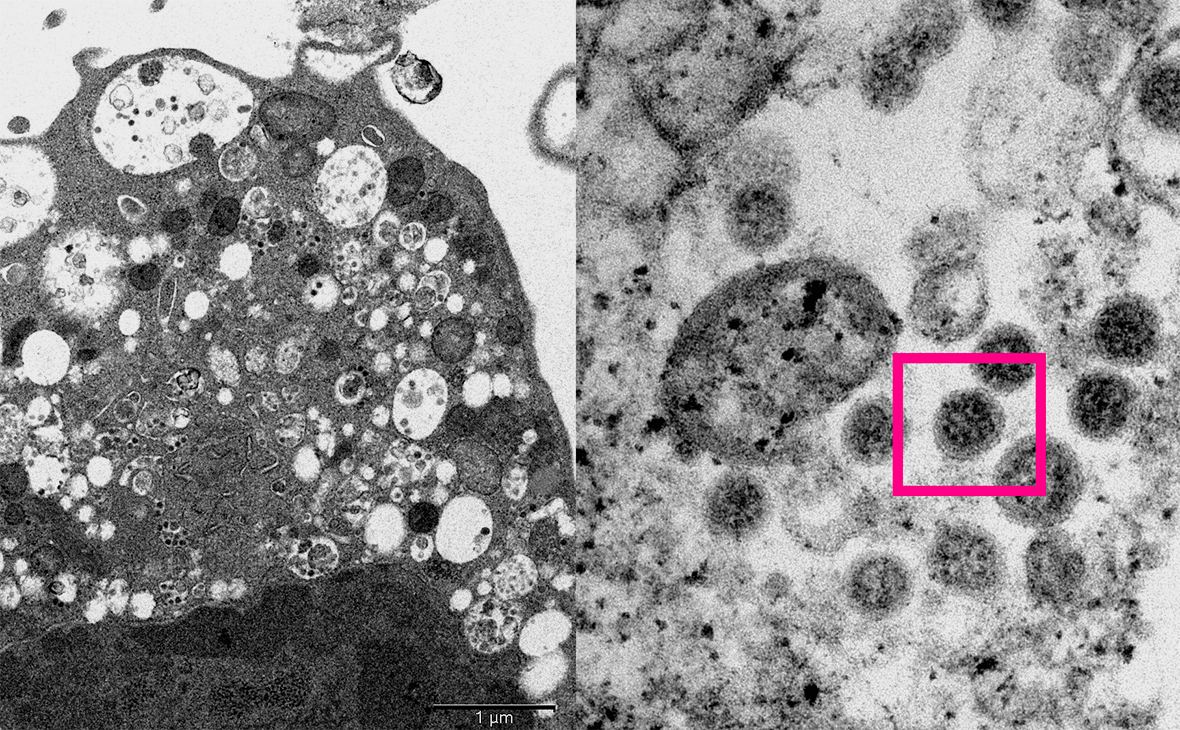

Фото: Центр геномики

Японские и американские ученые намеренно заразили омикроном хомяков и крыс, чтобы отследить, почему новая мутация протекает не так тяжело, как другие штаммы коронавируса. Оказалось, что омикрон меньше повреждает дыхательные пути и распространяется в этом участке организма с маленькой скоростью.

А вот исследователи из Гонконга изучали действие штамма на тканях человеческого организма. По результатам наблюдения за 12 образцами стало понятно, что омикрон распространяетсяся медленнее дельты.